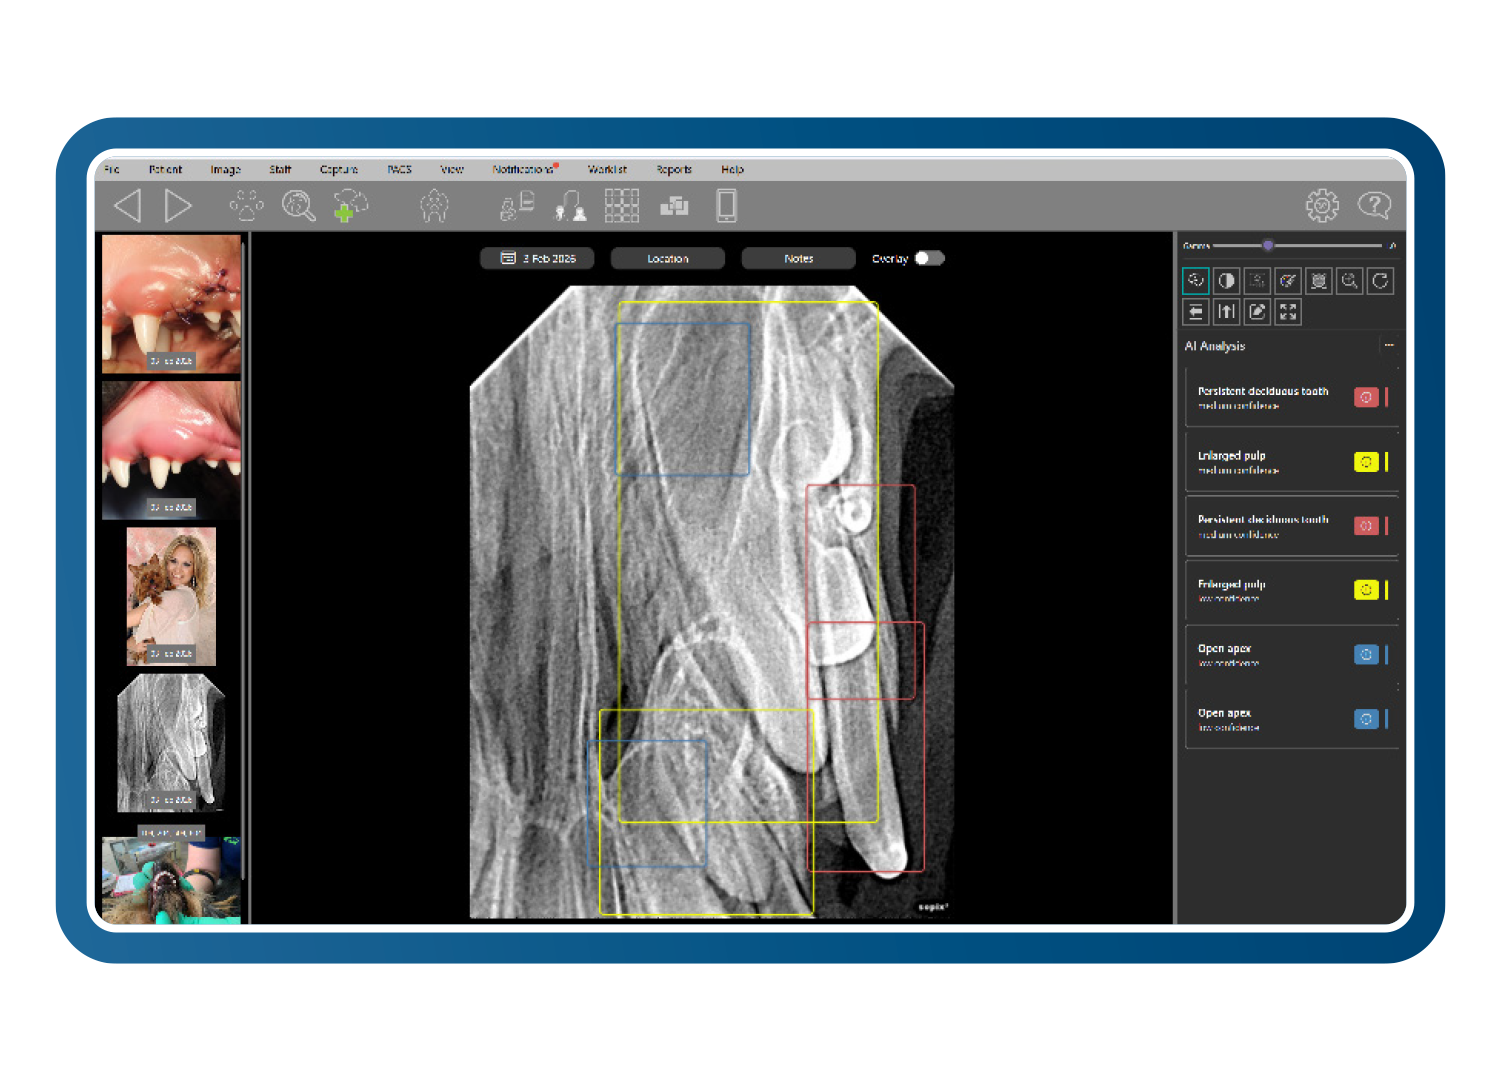

Optimización Clarity y reconocimiento de patologías (más de 70 afecciones)

Clarity identifica más de 70 patologías dentales y orales utilizando datos fotográficos y radiográficos. Entrenado con casos revisados por pares de odontólogos veterinarios certificados por el consejo, resalta anomalías en menos de 0,5 segundos, apoyando - sin sustituir - el diagnóstico clínico y acelerando una toma de decisiones segura y fundamentada.

Herramientas diagnósticas específicas para veterinaria

Las herramientas avanzadas de imagen veterinaria mejoran el detalle diagnóstico incluso a partir de imágenes subóptimas. El análisis de Clarity detecta cambios con una diferencia de contraste de tan solo un 2 %, mientras que los filtros inteligentes y la visualización en pseudocolor revelan la pérdida ósea y los detalles periodontales, reduciendo las repeticiones y convirtiendo imágenes de baja calidad en imágenes diagnósticas.